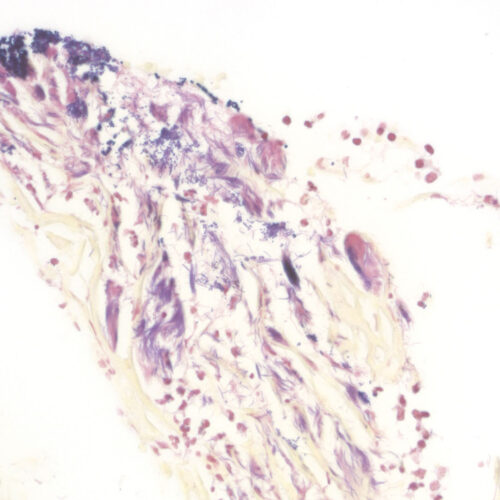

BioGram Histo kit

Five-reagent kit for identifi cation of bacteria according to Gram. For differentiation between Gram-positive and Gram-negative bacteria in histology sections.